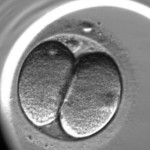

L’enregistrement du développement de l’embryon est le suivant :

Pour l’évaluation de la qualité des embryons on utilise la méthode d’analyse morphologique. Les embryons sont évalués selon les critères suivants : la quantité des blastomères, l’égalité des blastomères et la présence de fragmentation (des blastomères normaux qui ont été détruits). Cependant, cette méthode qui est la plus ancienne a ses inconvénients, elle est subjective (elle dépend de l’expérience et du niveau de l’embryologiste), un embryon est extrêmement variable durant son développement un embryon de mauvaise qualité de deux jours peut se transformer en un bel enfant en bonne santé. En ce moment, on utilise une nouvelle méthode d’évaluation de la qualité des embryons c’est l’embryoscopie. Son principe est le suivant : toutes les 10 ou 20 minutes on prend une photo de l’embryon en 7 couches, avec l’utilisation d’un programme informatique, on applique les images l’une sur l’autre pour en faire une video, c’est « le résumé » de chaque embryon. Avec l’utilisation d’un programme informatique spécifique, on mesure les paramètres clés du développement embryonnaire :

Le moment de la première division ;

Le commencement de la deuxième division (l’apparition du troisième blastomère)

La fin de la deuxième division (l’apparition du quatrième blastomère)